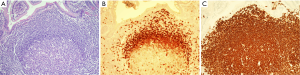

This organised tissue, termed MALT, is exemplified by the organised lymphoid tissue in the gut and is considered to include not only the organised lymphoid follicle but also the peri-follicular lymphocytes and plasma cells in the lamina propria, the intraepithelial B cells present in the dome epithelium and the mesenteric lymph nodes. The follicles in both the Peyer’s patches and the mesenteric lymph nodes have a well developed marginal zone external to the mantle zone (Figure 1). This compartment is not well developed in other lymph node groups but is seen in the spleen. It is thought this is related to areas that are associated with exposure to significant amounts of external antigen.

Structurally the lymphoid tissue in the gut mucosa consists of a lymphoid follicle with a reactive germinal centre that has the dark zone at the base with the light zone closest to the mucosal surface (Figure 2A). The germinal centre is surrounded by a well formed mantle zone that contains predominantly IgD positive naïve B cells and which is thickest below the surface epithelium and is rather thin where it abuts the muscularis mucosae (Figure 2B). External to this is the marginal zone that consists predominantly of slightly larger B cells with more abundant pale cytoplasm. There are other cell types in the marginal zone including plasma cells, T cells, macrophages and dendritic cells. This zone is also more developed below the surface where epithelial crypts are absent. The marginal zone abuts the overlying dome epithelium with infiltration of the epithelium by marginal zone B cells forming a lymphoepithelium (Figure 2A,C).